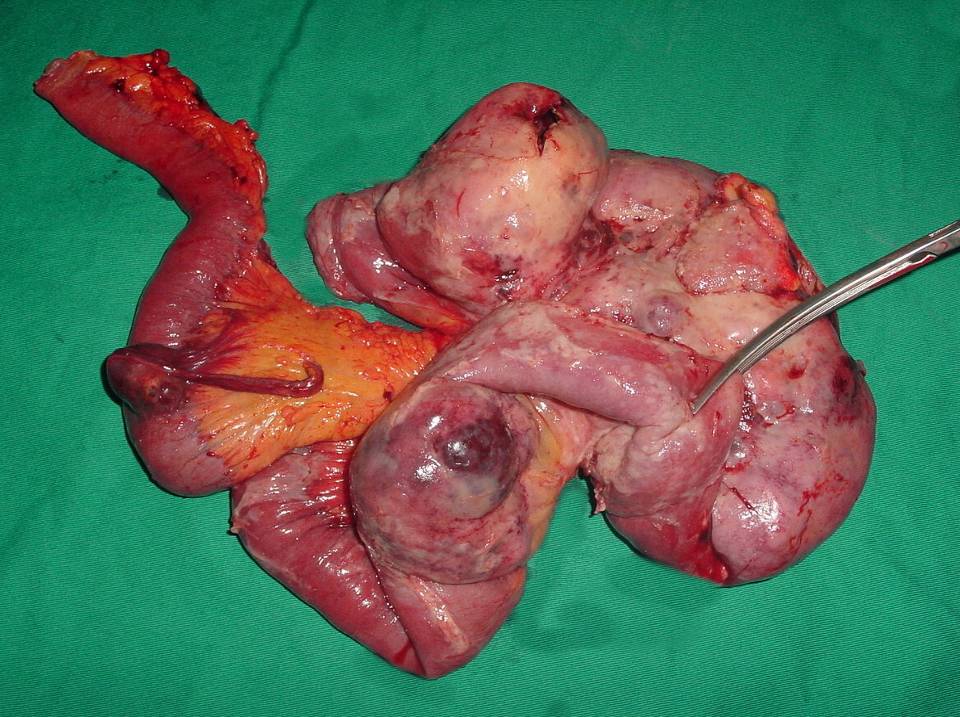

İleri Radyolojik Yöntemler

• Bilgisayarlı tomografi (BT)

• Manyetik rezonans görüntüleme (MR)

• Özellikle kitle oluşturan lezyonlarda.

• İlk aşamada kullanılmaları önerilmez.

• Konulmuş olan bir tanı sonrası yaklaşımı planlamada yardımcı olurlar.